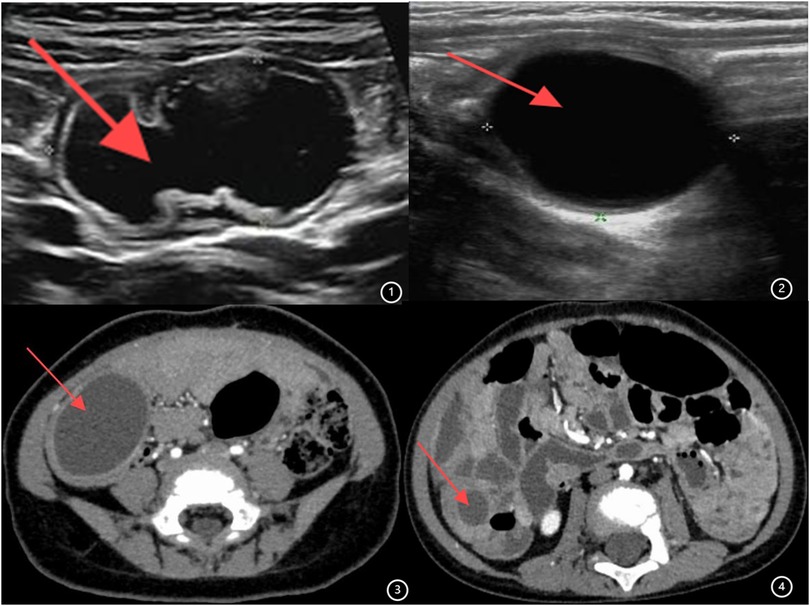

Ninety children [female: 43, 47.8%; male: 47, 52.2%; median age: 21.0 months (IQR: 6.4–48.0 months)] underwent surgery. Out of 90 cases, 59 (65.56%) presented abdominal pain symptoms, 19 (21.11%) displayed intestinal obstruction symptoms, and 12 (13.33%) were asymptomatic and identified incidentally. All patients underwent outpatient ultrasound examination, which indicated an intestine duplication abnormality (Figures 1, 2), followed by enhanced abdominal CT (Figures 3, 4) conducted upon admission to confirm the diagnosis. Laparoscopic exploration was performed after surgical contraindications were excluded.

Figure 1. (1,2) Ultrasound image of intestinal duplication malformation. (3,4) Enhanced CT image of intestinal duplication malformation.